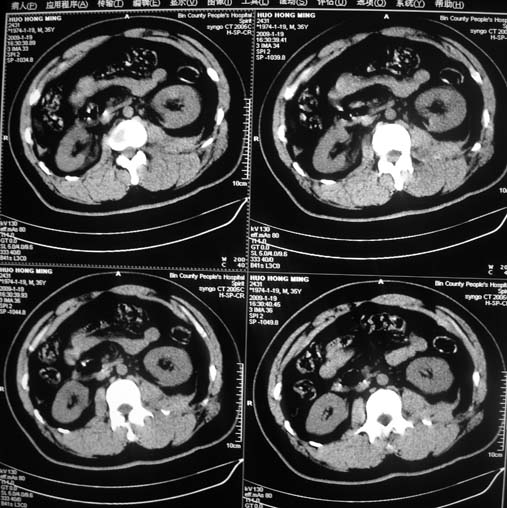

以下是引用余辉在2009-1-20 8:22:00的发言:[br]右侧肾上腺明显增大、边缘不光整,肯定有问题,结合患者病史考虑肾上腺挫伤、伴血肿形成。[br]另左肾后唇包膜下方可见局限性新月形高密度影,考虑肾包膜下出血[br]余同意楼上,建议增强排除脾破列

以下是引用随光逐影在2009-1-20 8:21:00的发言:[br]1)左侧多发肋骨及部分腰椎左侧横突骨折。2)左侧肾旁后间隙及同侧胸腔积血。3)左侧腰大肌肿胀。